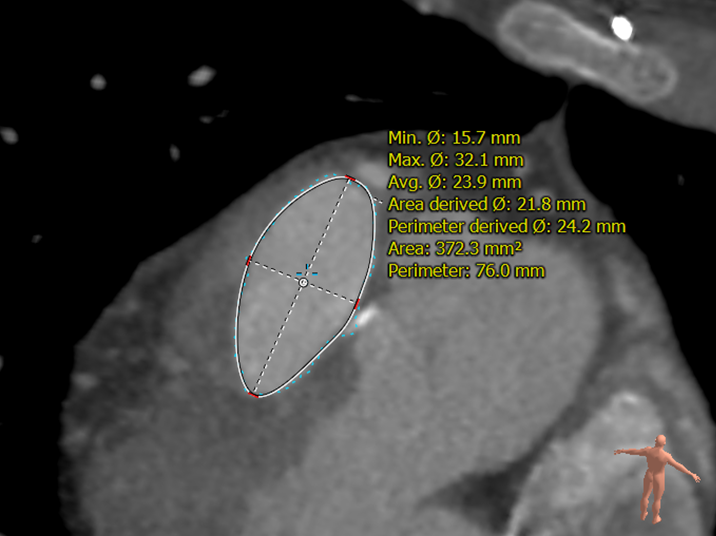

患者男性,23岁,法洛氏四联症根治术后20年,症状加重。超声提示肺动脉瓣重度返流、三尖瓣中度返流。术前行详细影像学重建与评估,主肺动脉腰部截面为不规则类圆形,径宽27-33mm,测算介入瓣植入后直径30mm。术中肺动脉造影测量与术前评估一致。手术经胸小切口入路,通过食道超声定位,经右室流出道穿刺植入30号Salus介入瓣,行经食道超声及肺动脉造影显示介入瓣植入位置理想,无瓣周漏及中央返流。

病例2 CT重建肺动脉

病例2 右室流出道截面呈不规则形